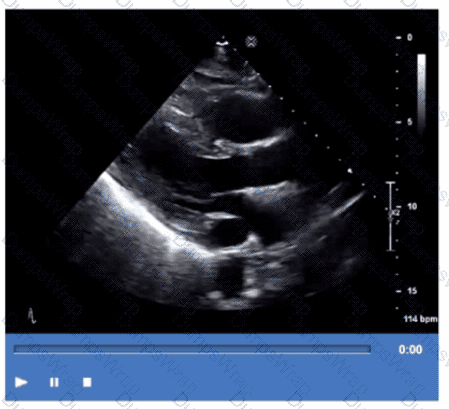

Which step is next in further evaluation of the abnormality shown in this video?

CExplanation:

Comprehensive and Detailed Explanation From Exact Extract:

The video suggests an atrial septal abnormality possibly a patent foramen ovale or interatrial shunt. To evaluate for right-to-left shunting across an atrial septal defect, the administration of agitated saline contrast with a Valsalva maneuver is the next best step.

Valsalva increases right atrial pressure transiently, promoting transient right-to-left shunting, making microbubbles visible in the left atrium if a shunt is present. Administration without Valsalva reduces sensitivity. The choice of arm vein (right or left) is less critical.

This diagnostic technique is well described in ASE adult congenital heart disease guidelines and echocardiography contrast protocols【12:ASE Contrast Echocardiography Guidelines†p.190-195】【16:Textbook of Clinical Echocardiography, 6e†p.575-580】.